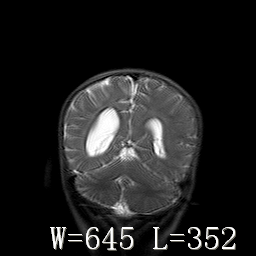

标题: PED3252:脑室增大。

女,3岁,3岁不会说话,阵发性抽搐、自伤。

考虑为梗阻性脑积水(中脑导水管狭窄)。

脑积水?脑发育不良?

侧脑室不规则,前后角尖角样,脑白质较少:考虑灰质发育不良可能

右侧额叶发育不良!

右侧额叶发育不良。

考虑,脑发育不良,胼胝体发育不全?(图片不全,矢状位?)